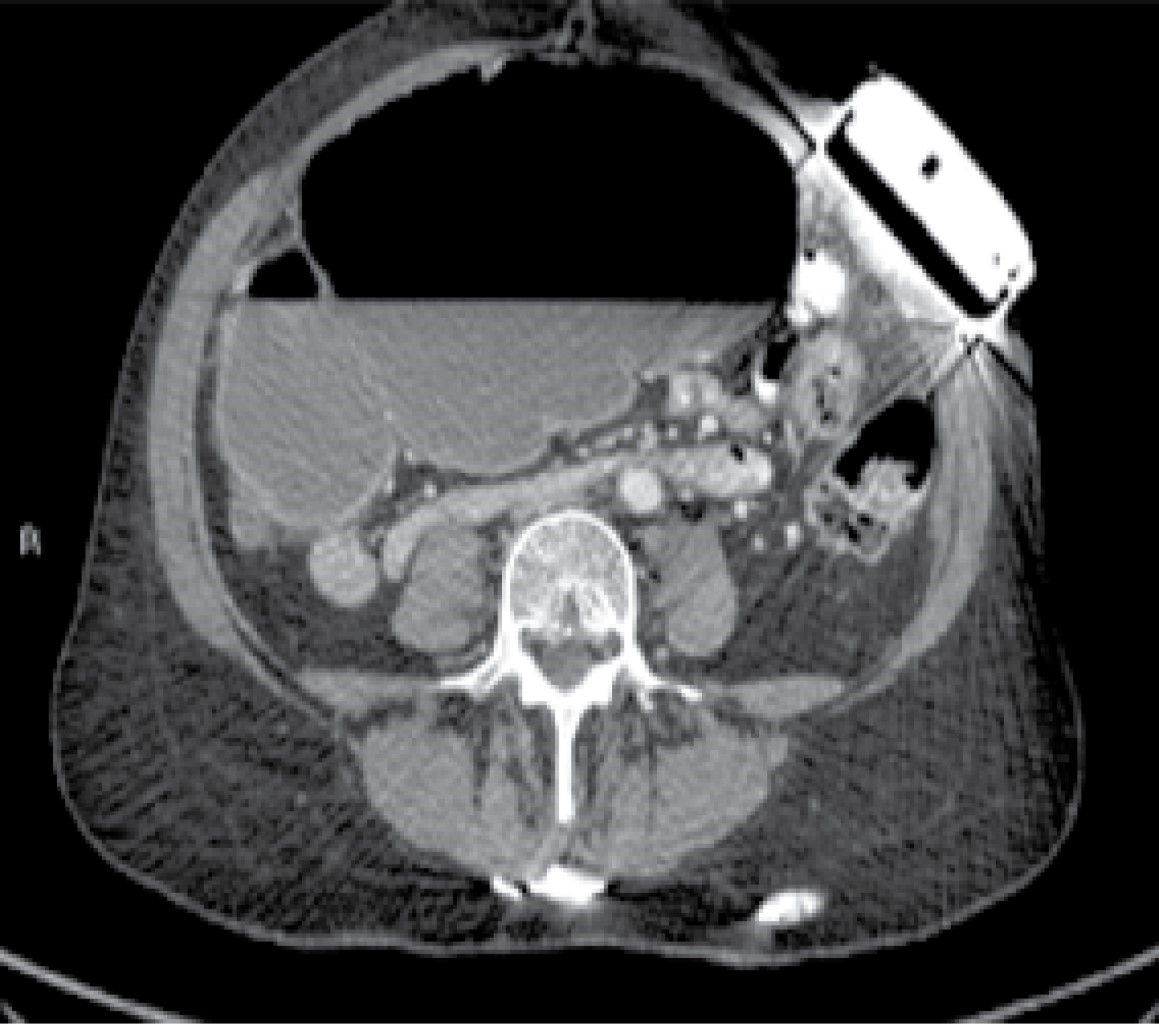

Laboratory studies were requested, which reported 12,000 leukocytes per cubic millimeter, seven-band forms, and serum lactate levels of 2.8 mmol/l. Subsequently, an abdominal tomography with double contrast was performed, finding significant cecal dilatation, the ascending colon and the proximal portion of the transverse colon, and a transition zone towards the distal third located in the left iliac fossa. Likewise, a supraumbilical abdominal wall hernia is found in the midline with scarce fatty tissue and omentum (Figures 1, 2, 3 and 4).

Figure 1